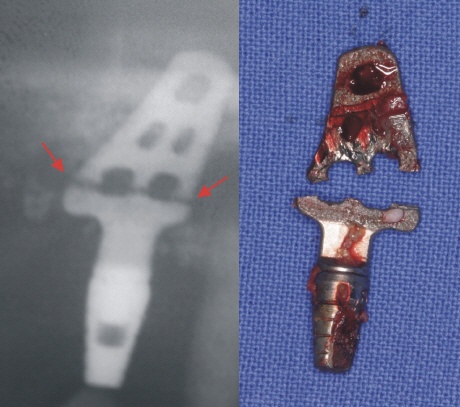

Implantatbruch (Implantatfraktur)

Ein Bruch des Implantats ist immer die Folge einer mechanischen Überbelastung. Bei den etablierten rotationssymmetrischen Implantaten gehören Brucherscheinungen des Implantats jedoch der Vergangenheit an.

Die sogenannten durchmesserreduzierten Implantate sind zwar aufgrund ihres geringen Durchmessers weniger bruchstabil, in bestimmten Situationen, wie beispielsweise zum Ersatz unterer Frontzähne oder oberer seitlicher Frontzähne, jedoch die einzige Möglichkeit. Bei einer fachgerechten Auswahl und Versorgung zeigen auch die durchmesserreduzierten Implantate kein erhöhtes Risiko für Frakturen (Brüche).

Bei den heute nicht mehr üblichen Blattimplantaten, wie auch bei den nicht zu empfehlenden Diskimplantaten, waren/sind Brucherscheinungen keine Seltenheit. Der große Nachteil hierbei ist, dass die zwangläufige Entfernung des gebrochenen Implantats oftmals einen erheblichen Knochendefekt hinterlässt.